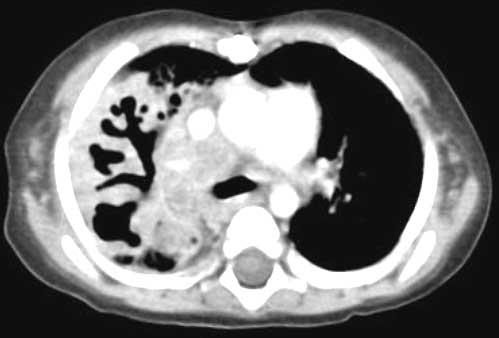

Below are CHEST CT results.

Enlarge

this CHEST CT.

WHAT

IS YOUR INTERPRETATION FOR THE CHEST CT?